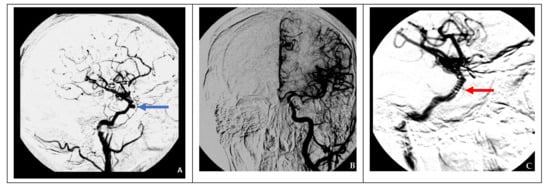

Figure 2. Endovascular surgical treatment in cases with good collateral circulation (clinical case 2). (A) A false aneurysm in the area of the cavernous segment of the right ICA (indicated by the blue arrow), (B) cerebral angiography of the left ICA demonstrating good collateral blood flow to the contralateral side, and (C) occlusion of a defect in the right ICA using two balloons (indicated by red arrows).

In cases of adequate collateral blood flow, endovascular occlusion at the ICA injury site using balloons in two cases and microcoils in three cases was performed (Figure 2).

In the presence of compensated (good) collateral blood circulation, occlusion of the internal carotid artery at the injury site is recommended. A latex balloon catheter was used for this purpose in cases 2 and 3. However, given the possibility of vessel recanalization due to a decrease in the balloon volume and the increased risk of enlargement of the existing defect in the vessel wall after balloon inflation, this technique is no longer used. An alternative to this technique is endovascular occlusion of the ICA with microcoils, used in cases 5 and 7.